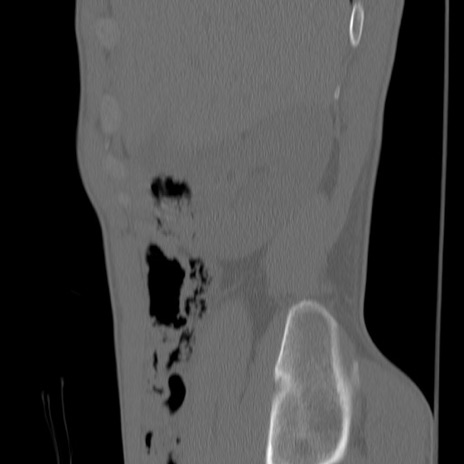

症例3 腰椎CT(矢状断像)

【症例】30歳代男性

【主訴】腰痛

【現病歴】本日旅行先で観光中に、友人と衝突し転倒し受傷。

【身体所見】麻痺なし、右下腿内側前面外側、左下腿内側に知覚鈍麻・しびれ

異常所見と診断は?

腰椎CT